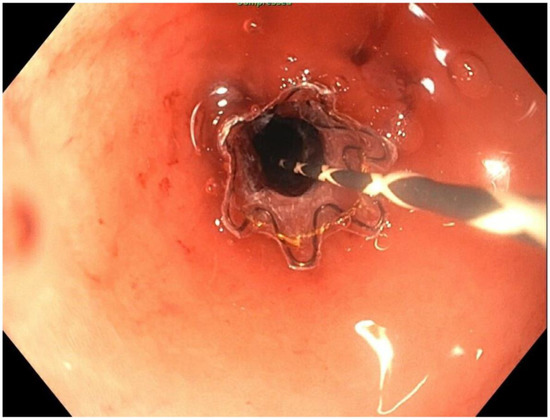

2. Detailed Case Description